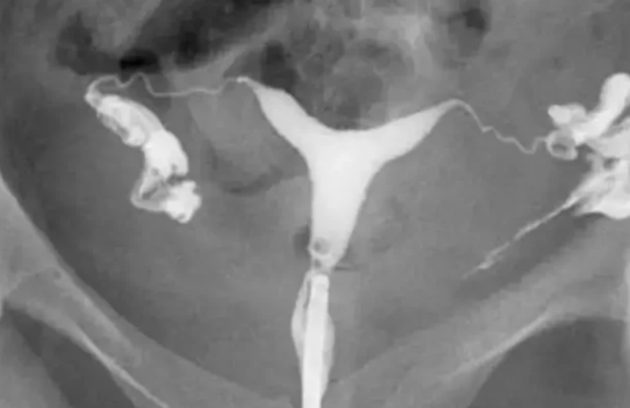

هیستروسالپنگوگرافی چیست و چه نقشی در تشخیص ناباروری دارد؟ هیستروسالپنگوگرافی (Hysterosalpingography – HSG) یک روش تصویربرداری تخصصی است…